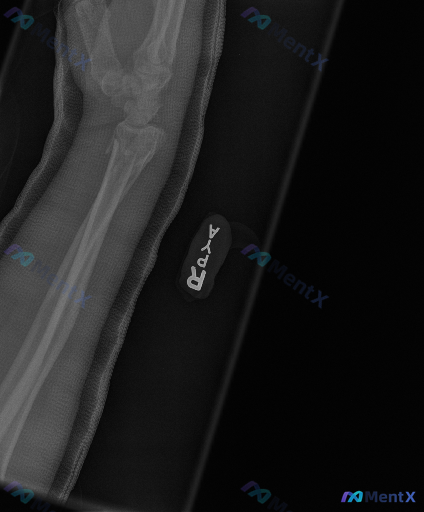

整理到一张放射影像资料,是右侧前臂X光片(正位)。 想请大家先读片,看看这张片子里有没有明确的异常?如果有,你认为最核心、最需要优先关注的是哪一组表现? (注:背景信息暂时先不放,就单看这张影像的表现来讨论)

整理到一份右侧前臂X光正位影像的病例资料,先和大家同步目前可见的表现: 1. 骨骼方面:桡骨远端干骺端区域可见骨皮质中断,远折端有向背侧/桡侧移位的迹象;尺骨茎突处也有骨皮质不连续的表现。 2. 关节方面:桡腕关节的正常解剖关系似乎有改变,下尺桡关节区域看起来间隙不太规整。 3. 软组织:桡骨远端周...